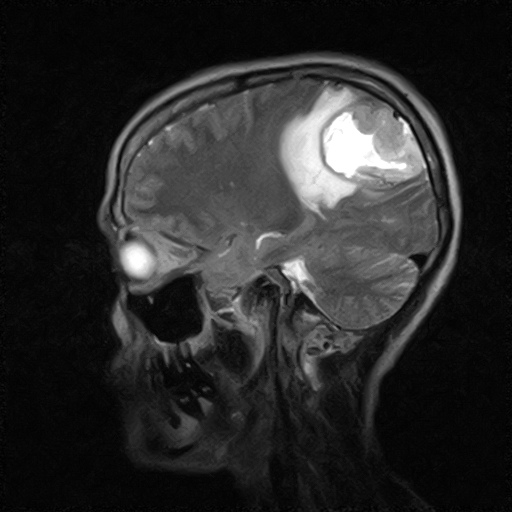

• RESONANCIA PATOLÓGICA DE CRANEO - MENINGIOMA -  SAG T1